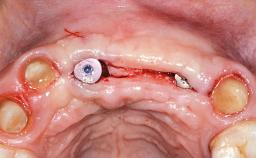

Replacement of an Upper Right Central and Lateral Incisor with an Implant-Supported Crown and a Distal Cantilever

This 20-year-old woman was referred to our department in July 2006. Four months earlier, she had experienced dental trauma to the anterior maxilla when traveling in South America. The emergency treatment included emergency root canal treatment of teeth 12 and 11. Tooth 21 was also subjected to endodontic treatment later. At the initial examination, the patient was not in pain but reported increased mobility of tooth 12. The clinical examination revealed a high smile line, medium thickness of the soft tissue, and rectangular tooth forms. Discoloration of tooth 12 was evident. The periapical radiograph provided by the referring dentist indicated a fracture line at both teeth 12 and 11. A cone-beam computed tomography (CBCT) scan confirmed these fractures. No pathology was found to be associated with tooth 21.